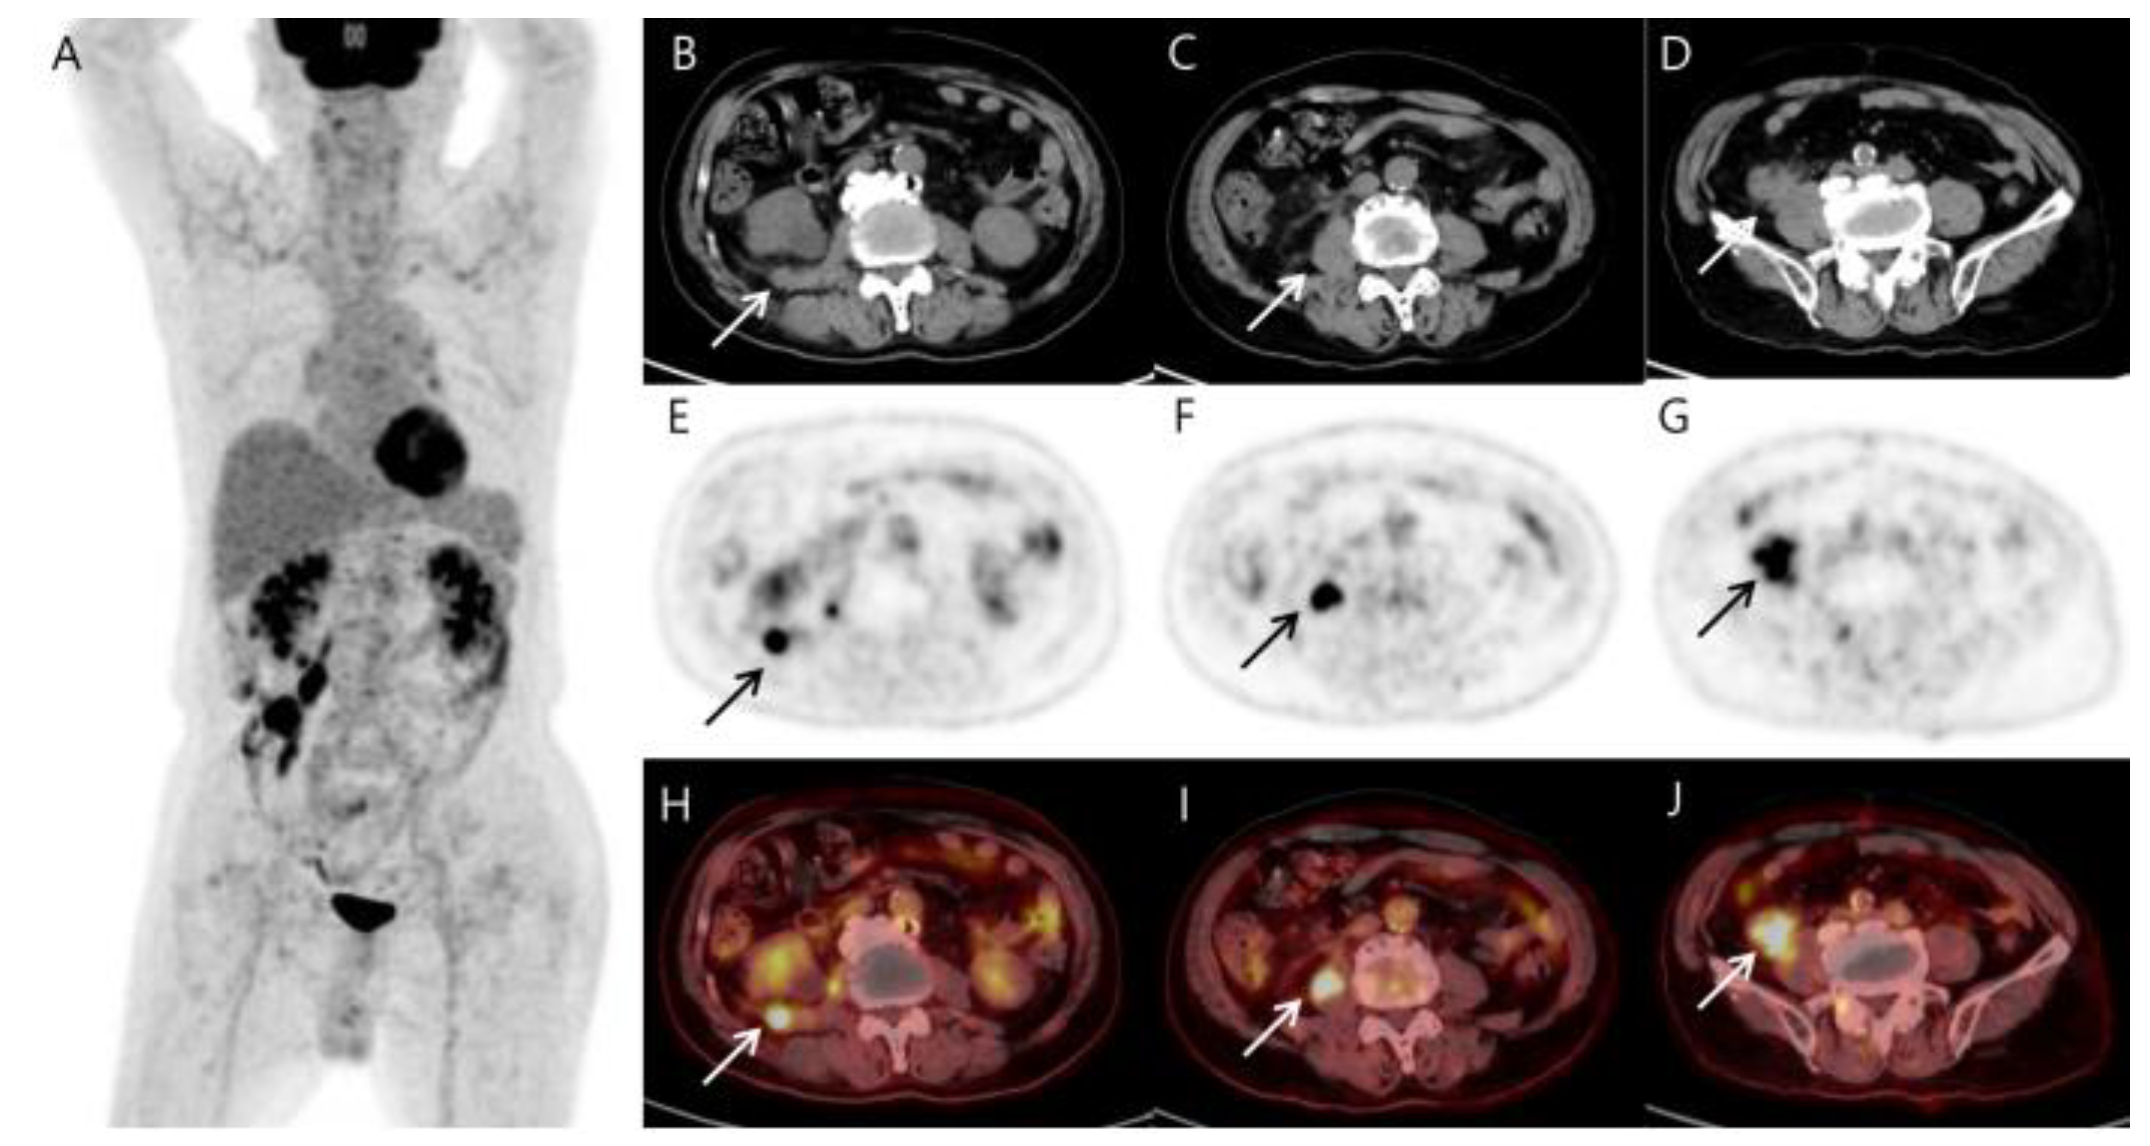

Figure 2.

MIP (A), CT (B–D), PET (E–G), and fusion PET/CT (H–J) of the 18F-FDG PET/CT images reveal several hypermetabolic soft tissue nodules (arrows) involving the terminal ileum (SUVmax 17.87), right psoas muscle (SUVmax 14.87), and reptroperitoneum (SUVmax 12.22). The terminal ileal mass shows a comet-tail-like pattern of increasing absorption toward the back, suggesting invasion into the psoas muscle. Other than the above-described area, no significant abnormal findings in other parts of the body are included in the image. As shown in the MIP image, it differs too much from the typical prostate cancer metastasis that spreads from bottom to top along lymph nodes to be considered prostate cancer metastasis. Additionally, it is not appropriate to consider it a small intestinal adenocarcinoma and metastasis because the patient has no symptoms. The patient had previously been treated for lymphoma, and based on the 18F-FDG PET/CT findings, we first considered the possibility of recurrent lymphoma or sarcoma.